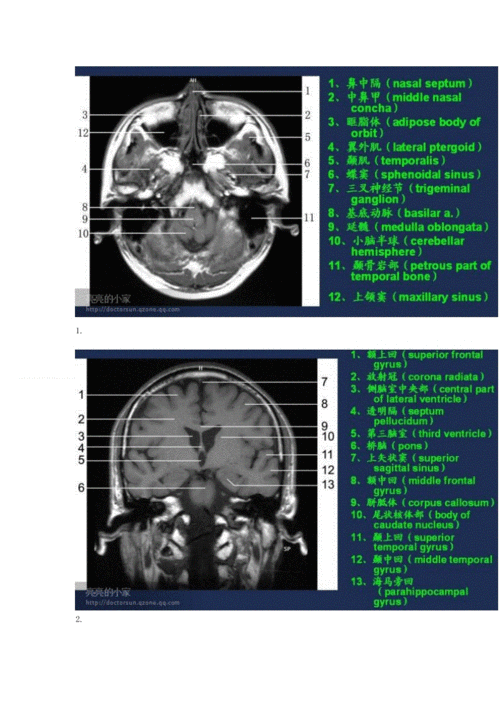

脑部主要结构mri横断位解剖

高清mri图颅脑磁共振mri解剖